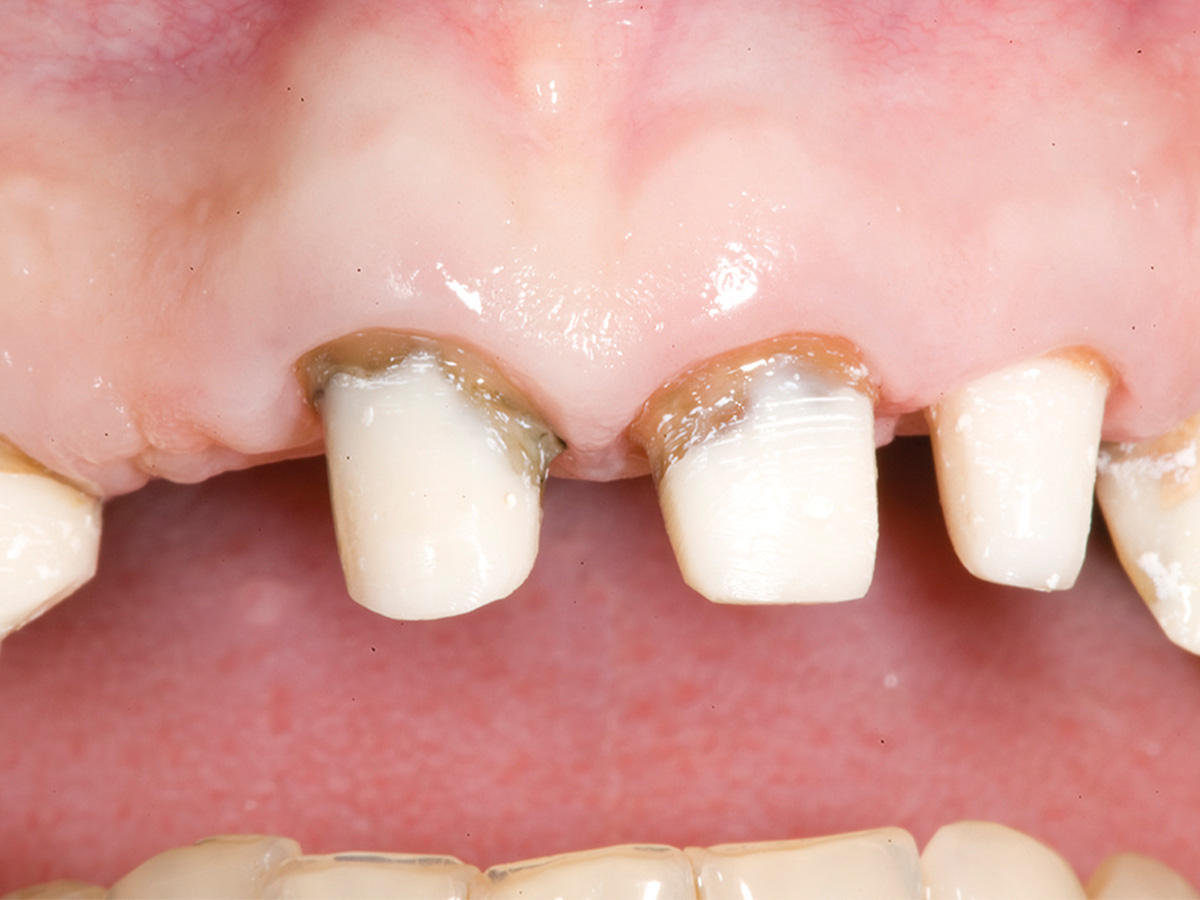

Abbildung 7

Situation 1 Woche post-OP mit Provisorium.